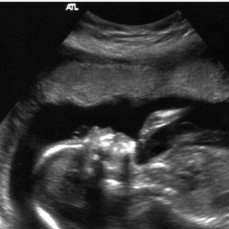

Првото движење на бебето во стомакот на мајктаа е еден од најемотивните моменти за идните родители.

Плод